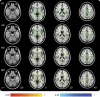

Methods: Fifty-three patients were scanned an average of 6 days postinjury (range = 1-14 days). Twenty-three patients were rescanned 1 year later. Thirty-three matched control subjects were recruited. At the time of scanning, participants completed cognitive testing. Tract-Based Spatial Statistics was used to conduct voxel-wise analysis on diffusion changes and to explore regressions between diffusion metrics and cognitive performance.

Results: Acutely, increased axial diffusivity drove a fractional anisotropy (FA) increase, while decreased radial diffusivity drove a negative regression between FA and Verbal Letter Fluency across widespread white matter regions, but particularly in the ascending fibers of the corpus callosum. Raised FA is hypothesized to be caused by astrogliosis and compaction of axonal neurofilament, which would also affect cognitive functioning. Chronically, FA was decreased, suggesting myelin sheath disintegration, but still regressed negatively with Verbal Letter Fluency in the anterior forceps.